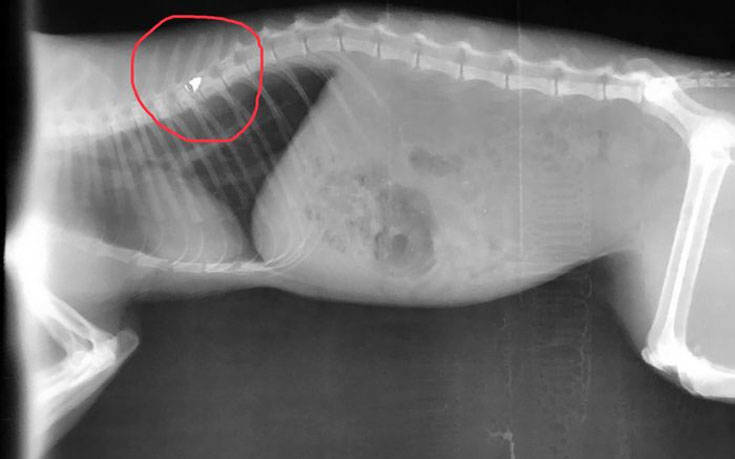

Σύμφωνα με τα όσα κατατέθηκαν ενώπιον των αστυνομικών και δικαστικών αρχών, ο εκπαιδευτικός που είναι και Λυκειάρχης σε σχολείο του δήμου Λαμιέων, πυροβόλησε το άτυχο ζώο με αεροβόλο, με τη βολίδα να σφηνώνεται στη σπονδυλική του στήλη και να μένει παράλυτο.

«Σε 16 μήνες φυλάκιση καταδικάστηκε σήμερα 12 Ιουλίου 2019 εκπαιδευτικός, διευθυντής σε Λύκειο της Δευτεροβάθμιας Εκπαίδευσης του Δήμου Λαμιέων, ο οποίος εν ψυχρώ πυροβόλησε και άφησε παράλυτο από την μέση και κάτω έναν αδέσποτο γάτο. Το άτυχο ζώο πυροβολήθηκε από τον δράστη με αεροβόλο όπλο την ώρα που ζευγάρωνε.